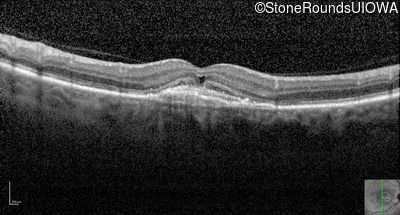

Optical Coherence Tomography - Right - 20/250

Exemplar / OCT Stack

Infrared Fundus Photograph - Right - 20/250

Exemplar